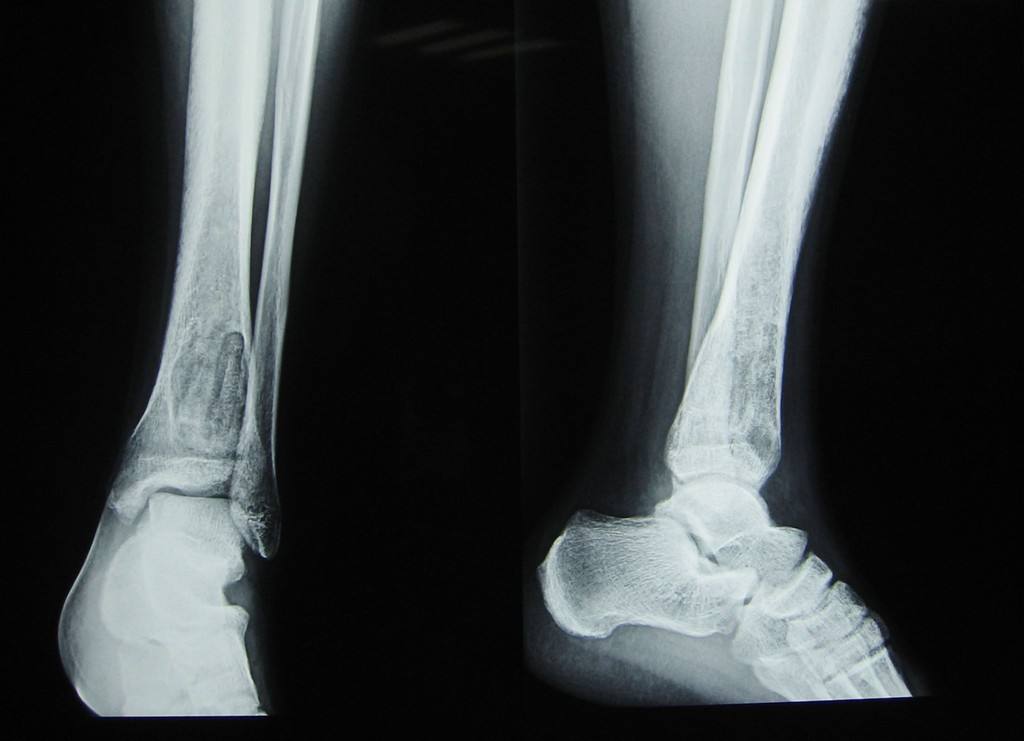

骨化性纖維瘤(ossifying fibroma)是為較為常見的頜骨良性腫瘤,邊界清楚。組織學(xué)上,腫瘤由富含細(xì)胞的纖維組織和表現(xiàn)多樣的礦化組織構(gòu)成。根據(jù)腫瘤中所含纖維成分和骨質(zhì)成分比例的多寡,可分別命名為骨化性纖維瘤及纖維骨瘤。2005年WHO新分類簡(jiǎn)化了骨相關(guān)病變的分類和命名,以“骨化性纖維瘤”代替了“牙骨質(zhì)-骨化纖維瘤”,并將“青少年小梁狀骨化纖維瘤”和“青少年沙瘤樣骨化纖維瘤”作為骨化纖維瘤的兩種組織學(xué)變異型。